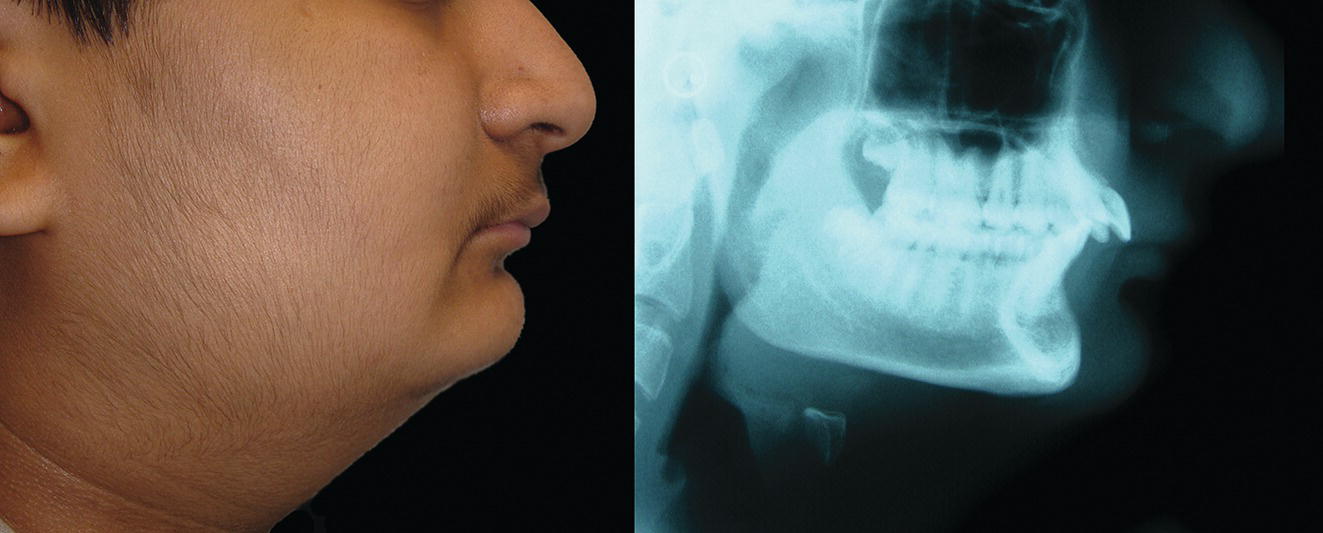

See ‘terminology’ section in Chapter 16. The mandible, the bone of the lower jaw, is one of the most important bones in the craniofacial complex; its anatomy and structural relationships are thus highly significant (Figure 19.1). For descriptive purposes, the mandible may be said to be comprised of a number of subunits: the two main parts are the ramus, which is for articulation and the insertion of jaw‐moving muscles, and the body (corpus), which carries the dentition (Figure 19.2). The body is horseshoe‐shaped when viewed from above, and the two vertical rami project upwards one from each posterior end of the body. The posterior border of the ramus projects upwards as the condylar process, which consists of a neck, expanding into a condylar head or condyle. The body of the mandible projects up around the teeth as alveolar bone, which forms the walls of the tooth sockets. After loss of a tooth the living alveolar bone atrophies. Extensive tooth loss may thereby lead to a reduction in lower anterior face height due to loss of the dentoalveolar process (Figure 19.3). The inferior border of the mandible provides the demarcation between the lower face and neck. The anterior extremity of the mandibular body is the highly variable prominence of the mandibular or mental symphysis (bony chin). Typical morphology: The morphology of the mandible (excluding the bony chin) is relatively consistent, depending on the basic type of dentofacial deformity with which a patient may present, e.g. ‘Class II’, ‘Class III’, ‘short face’ or ‘tall face’. Conversely, the morphology of the bony chin is highly variable and will be described in detail in Chapter 20. Gonial angle (Ar‐Go‐Me): This is a measure of the angle formed between the slope of the posterior border of the mandibular ramus and the mandibular plane. It helps to describe the morphology of the mandible, in particular the relationship between the ramus and the body (Figure 19.4). It is highly correlated with the mandibular plane angle. An increased gonial angle is associated with posterior mandibular growth rotation, and a reduced gonial angle is associated with anterior mandibular growth rotation. In order to determine the relative contribution of the ramus and body of the mandible to mandibular morphology, the gonial angle may be divided into two parts, an upper and lower component, by drawing a facial depth line (nasion‐gonion). The upper component of the gonial angle (50° ± 2°) identifies the inclination of the ramus and the lower component identifies the inclination of the body of the mandible (Figure 19.5).3 Figure 19.1 (A) Oblique right lateral view. (B) Superior view. (C) Oblique left posterior view. Figure 19.2 Mandibular subunits: Figure 19.3 Extensive tooth loss results in resorption of the alveolar process and thereby a reduction in the lower anterior face height; the mandible will rotate anteriorly bringing the chin characteristically closer to the nose. (Head of an Old Man, c. 1487–90, Leonardo da Vinci, Codex Trivulzianus, Sforza Castle, Milan.) Figure 19.4 (A) Reduced, acute gonial angle. (B) Increased, obtuse gonial angle. Figure 19.5 The gonial angle may be divided into an upper and lower component in order to determine the relative contribution of the ramus and body inclination to mandibular morphology. Mandibular growth rotations: Growth rotations of the mandible occur when there is a discrepancy in the amount of anterior and posterior lower facial heights. It is important to bear in mind that the amount of rotation is masked to some extent by periosteal remodelling and dentoalveolar adaptation. Forward (anterior) rotation of the mandible, in the direction of mouth closing, is due to increased posterior vertical facial growth relative to anterior vertical facial growth (Figure 19.6A). Backward (posterior) rotation of the mandible, in the direction of mouth opening, is due to reduced posterior vertical facial growth relative to anterior vertical facial growth (Figure 19.6B). Björk4 described seven structural signs found on a lateral cephalometric radiograph, which may provide an indication to the pattern of mandibular growth (Table 19.1 and Figure 19.7). Inferior border of the mandibular body: The lower border of the mandible should be well‐defined, providing distinct separation of the lower face from the neck. This region will be relatively unattractive in the absence of such demarcation between the lower face and neck, which may be due to skeletal and/or soft tissue factors (Figure 19.8): Figure 19.6 (A) Forward (anterior, anticlockwise) rotation of the mandible, in the direction of mouth closing, is due to increased posterior vertical facial growth relative to anterior vertical facial growth. (B) Backward (posterior, clockwise) rotation of the mandible, in the direction of mouth opening, is due to reduced posterior vertical facial growth relative to anterior vertical facial growth. Table 19.1 Björk’s seven structural signs indicating the pattern of mandibular growth rotation For the numbers refer to Figure 19.7. A thorough clinical evaluation of this region is required, involving clinical inspection and palpation. The lateral cephalometric radiograph, orthopantomograph (OPT) and where necessary three‐dimensional reconstruction of the mandible permits more accurate analysis of the inferior mandibular border. When skeletal and soft tissue factors coexist, surgical correction to redefine the natural demarcation in this region may involve augmentation of the lower mandibular border and gonial angles in conjunction with rhytidectomy. Figure 19.7 Björk’s seven structural signs, which may be used to indicate the pattern of mandibular growth (for an explanation of the numbers, refer to Table 19.1). Figure 19.8 Indistinct inferior border of the mandible. Mandibular micrognathia (a small mandible) may have reasonable proportionality between the ramus and body. Although hypoplasia of the mandible may affect the ramus, body or both, syndromic mandibular deficiency is often due to a short mandibular ramus. The surgical technique of distraction osteogenesis may be used to differentially lengthen the ramus and/or the body of the mandible. The craniofacial dimensions of patients with craniofacial syndromes in particular may not fit into normal ranges of variability. Therefore, the use of proportional analysis rather than comparison with population ‘norms’ is a useful method of evaluating the specific area (ramus or body), direction and extent of lengthening that may be required. The characteristic feature of sagittal mandibular deficiency, and the most common complaint from the ‘Class II’ patient, is the retruded position of the chin relative to the rest of the face in profile view. It is important to distinguish true skeletal mandibular deficiency from relative mandibular deficiency. True sagittal mandibular deficiency may be due to: Relative mandibular deficiency may be due to: Table 19.2 Normal mandibular dimensions (white Caucasian adults) Refer to Figure 19.9. Figure 19.9 Mandibular dimensions (for normative values see Table 19.2). The aetiology of mandibular deficiency may result from a combination of relative and true mandibular deficiency. The diagnostic features of sagittal mandibular deficiency depend to a great extent on the lower anterior facial height (LAFH). In patients with sagittal mandibular deficiency and a normal or reduced LAFH, the diagnostic features are (Figure 19.10): Figure 19.10 Sagittal mandibular deficiency with a reduced lower anterior facial height. Figure 19.11 Sagittal mandibular deficiency with an increased lower anterior facial height. In patients with sagittal mandibular deficiency and an increased LAFH, the diagnostic features are (Figure 19.11): The aetiology of Class III jaw deformity, in particular mandibular excess, has a very strong genetic basis.7 The familial tendency of Class III deformity may be frequently observed in members of the same family. A famous example is of the Hapsburg dynasty, one of the German royal families. Over 23 generations, portrait painters have captured images of the Hapsburgs, and they all exhibit the same mandibular prognathism and protrusive lower lip, often termed the ‘Hapsburg jaw’ (Figure 19.12). In addition, evidence from twin studies has suggested the strongest genetic predisposition for Class III malocclusion, with concordance in identical twins six times higher than in non‐identical twins for mandibular prognathism.8 Although there is a strong familial occurrence, there seems to be no association with sex, with different modes of transmission in different families or populations.9 Edward Angle, described as the father of modern orthodontics, recognized early in the twentieth century that severe mandibular excess could only be corrected through a combination of orthodontics and mandibular surgery (Figure 19.13).10 The characteristic feature of mandibular excess, and the most common complaint from the ‘Class III’ patient, is the prominence of the chin and lower lip relative to the rest of the face in profile view (Figure 19.14). It is important to distinguish true skeletal mandibular excess from relative mandibular excess. Figure 19.12 The prominent ‘Hapsburg jaw’ and protrusive lower lip of the Hapsburg dynasty is evident in the portraits of (A) Charles V, Holy Roman Emperor (1500–58) and (B) Charles II of Spain (1661–1700). Figure 19.13 The ‘chin retractor’ of Edward Angle was a predecessor to the chin cup (chin cap) used by orthodontist in the attempt to correct mandibular excess in young patients by restraining mandibular condylar growth; Angle later recognized the limitations of such appliances. True sagittal skeletal mandibular excess may be due to: True skeletal mandibular excess must be distinguished from relative (apparent) mandibular excess. Conditions in which the mandible appears excessively prominent are: Figure 19.14 The characteristic feature of mandibular excess is the prominence of the chin and lower lip relative to the rest of the face in profile view. The two contrasting heads demonstrate an attractive profile (left panel) and a ‘Class III’ profile with mandibular excess and protrusive lower lip (right panel). (Michelangelo, c. 1516–24, The Ashmolean Museum, Oxford.) The aetiology of mandibular excess often results from a combination of relative and true mandibular excess.